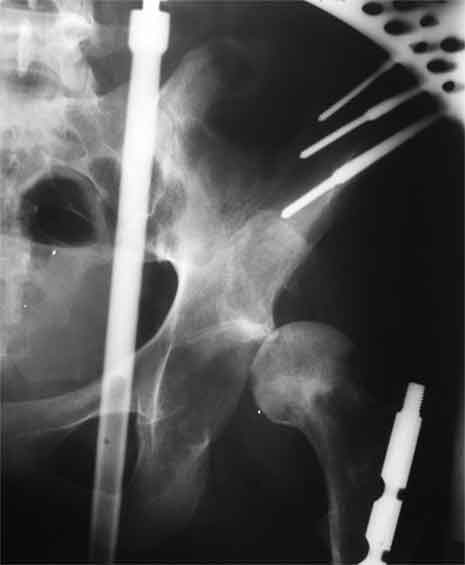

Насчет 8 см согласен с А.Н. Челноковым, это наверное ортопедическое за счет приводящей, сгибательной контрактуры и, возможно, колена. на ликвидацию укорочения у нас обычно уходит около 2-х нед. снимки в приложении, возможно не очень показательные, но других с ходу не нашел, завтра еще поищу.

Еще пара фото, ситуация несколько иная, задачи те же, открытое вправление застарелого вывиха в 2002, молодой возраст. Сейчас госпитализирована для эндопротезирования.

AV> опираясь на стул. На ногу не наступает. Укорочение 8 см. Иногда

А за счет чего такое укорочение? По снимку не видно соответствующего дефекта. Ну плюс приводящая контрактура - но все равно как-то уж больно много. Может, сделать снимки и таза обзорный с обоими проксимальными отделами бедра, и коенный суставов с приложенной линейкой какой?

Судя по снимку, максимум истинное укорочение около 4 см, что может быть коррегировано интраоперационно. Вопрос в другом: куда ставить ацетабулярный компонент в истинную или во вновь сформированную ( впадина диспластичная).

The X ray that you provided does not show 8 cm of shortening. Perhaps you could send one showing the whole pelvis and proximal femurs.

До травмы проблем с ногой не было. Укорочения, болей и т.п. не отмечал. Сегодня перемерял укорочение - меньше 7 см намерять не

По уровню малых вертелов (с учетом рентгеновского увеличения) получается 5 см. Клинически ногу низвести путем тракции невозможно. Из движений - сгибание до 40*, остальные движения "символические".